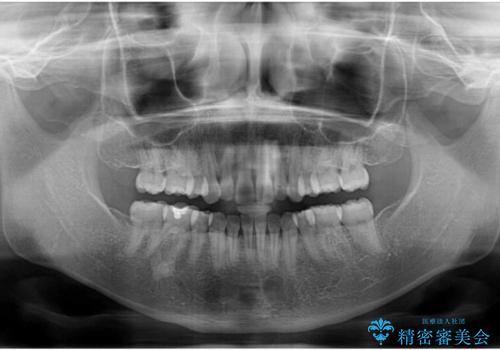

元々上下正中の位置はずれていましたが、治療中によりズレが大きくなったので、元の位置に戻すため治療期間を余計に要しました。

横顔の印象が大きく改善され、患者様には大変満足していただきました。